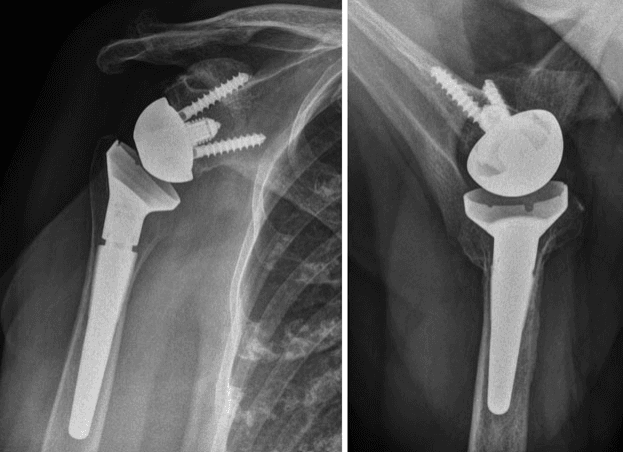

- Reconstrucția articulației: Endoprotezarea articulației cu proteză anatomică sau proteză inversată.